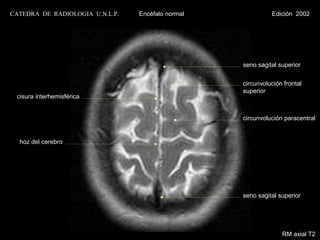

CATEDRA DE RADIOLOGIA U.N.L.P.   Encéfalo normal             Edición 2002

seno sagital superior

circunvolución frontal

superior

cisura interhemisférica

circunvolución paracentral

hoz del cerebro

RM axial T2